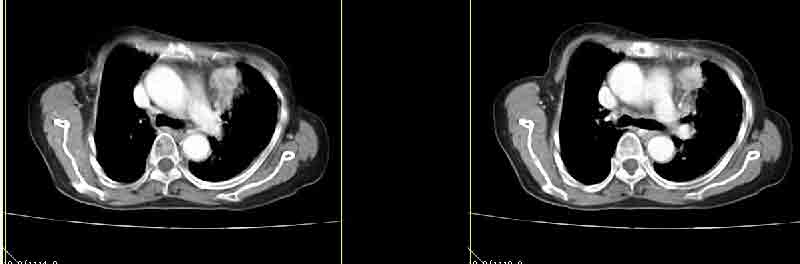

女77岁因左侧胸痛伴咳嗽入院;提示:病灶平扫45hu,强化145hu补充:双肺内未闻及干湿罗音

定位肺内,强化显著(100hu以上),考虑感染性病变先,抗炎后复查排除占位。

我的诊断意见:左肺上叶前段肺癌伴节段性不张。

在不张的肺内见到不规则的软组织,而且强化是不均匀的(该点可能是我的图像作得不好的原因)。

强化密度略高于肌肉 考虑周围型肺癌【小箭头为容积效应现象】

左上肺前段可见分叶团块影,强化明显,周围见带状不张影,右肺结节,左肺沿肺纹模糊片状影,考虑左上肺占位,肺癌可能性大。